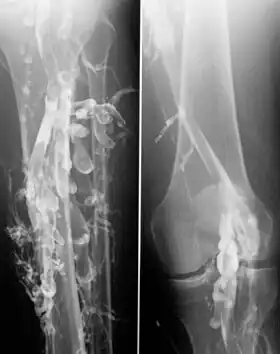

Venography in a patient with deep vein thrombosis

Contrast venography is the gold standard for judging diagnostic imaging methods for deep vein thrombosis; although, because of its cost, invasiveness, and other limitations, this test is rarely performed.[1]